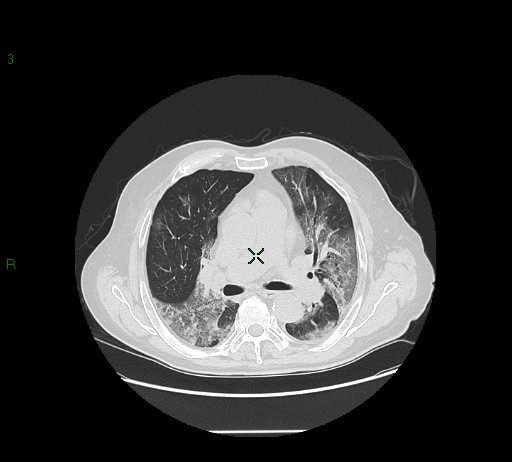

57-year-old male

patient smoker with COPD. No epidemiologic risk either exposure to Covid-19 patients.

The patient was admitted

to ED for...